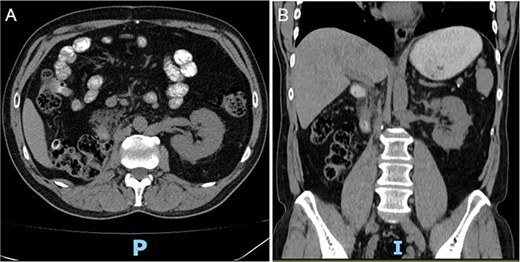

The authors present the case of a 60-year-old male patient with a recent diagnosis of T2a melanoma on the back, with no indication for adjuvant therapy, who underwent an abdominopelvic computed tomography with an incidental finding of a hypervascular solid mass in the right lower renal pole, compatible with an organic lesion measuring 8.5 × 7 × 8 cm invading the renal vein and the azygos vein, with intrathoracic extension (Fig 2A–D). The patient presents a vascular anomaly characterized by agenesis of the retrohepatic portion of the IVC. The hepatic veins drain directly into the right atrium, while the azygos vein serves as an alternative venous pathway, draining into the superior vena cava. A thrombus extends through the azygos vein into its intrathoracic portion.

(A–D) Abdominopelvic contrast-enhanced computed tomography prior to neoadjuvant therapy showing a lesion in the right kidney with associated mural thrombus extends through the azygos vein in the sagittal section.

Follow-up CT imaging (Fig. 3A–D) showed a reduction in both the tumor and thrombus size, leading to the classification of the thrombus from Stage IV to Stage III according to the Mayo Clinic classification.

(A–D) Abdominopelvic contrast-enhanced computed tomography post-neoadjuvant therapy showed a significant reduction in tumor size and the involvement of the thrombus in the azygos vein.